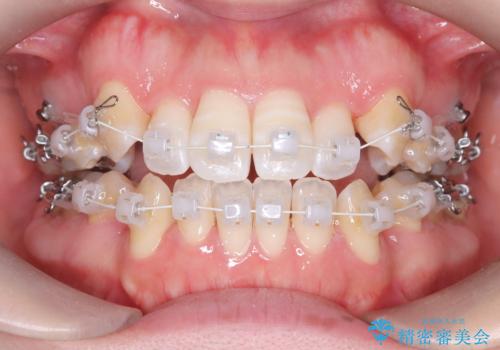

- 前歯のガタガタや八重歯の位置の乱れが気になっていた患者様に対して、ワイヤー矯正を行いました。矯正の過程で、スペースを確保するために上下左右の小臼歯を抜歯し、歯全体のバランスと機能性を考慮しながら理想的な歯列に仕上げました。

治療後は、前歯の位置や噛み合わせが整い、見た目も機能面も大きく改善されました。きれいな歯並びを得ることができ、患者様にも非常に満足していただけました。

抜歯によって確保したスペースを活用し、効率的に歯列を整えました。前歯のガタガタと八重歯が解消され、自然で美しい仕上がりを実現しました。